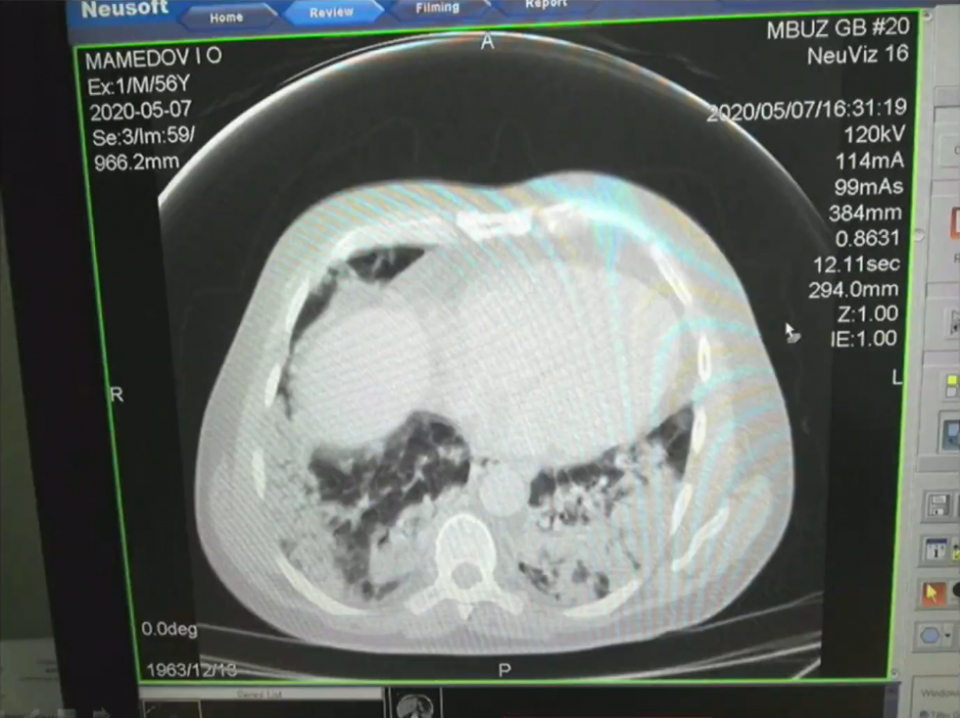

Рентгеновские снимки легких больных коронавирусом в ходе заседания оперштаба показала Татьяна Быковская.

Снимки она продемонстрировала с разрешения пациентов.

— Всё, что темное, — это ткань легкого, а светлое — так называемое матовое стекло. Это показатель того, что наступает необратимый процесс. Легкие наполняются кровью, и дышать пациент самостоятельно не может, — пояснила Быковская.

Причем легкие поражаются с большой скоростью, иногда за несколько часов область поражения увеличивается в несколько раз.